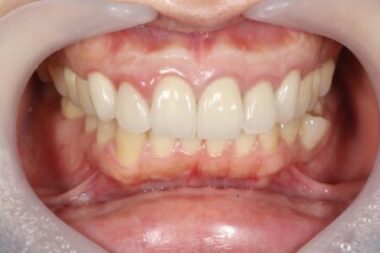

画像がこちらになります。

治療後画像①|【症例】セラミック治療後に発症した根尖性歯周炎に対する歯根端切除術|目白マリア歯科

左:術後3日 右:術後3ヶ月

治療後画像②|【症例】セラミック治療後に発症した根尖性歯周炎に対する歯根端切除術|目白マリア歯科

術後1年

術後およそ2週間で、患者様が訴えていた違和感は大きく改善されました。

その後も3ヶ月、1年と経過を追って確認した結果、現在に至るまで外科手術による瘢痕はほとんど見られず

美しい歯のラインを維持したまま、無事に治療を完了することができました。

また、心配されていた審美的な問題もなく、自然な見た目を保ったまま治療を終えることができました。